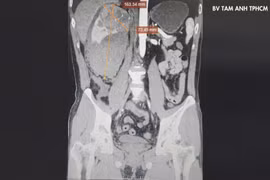

Diễn tiến âm thầm, phát hiện u thận đã nặng 1,2kg

Người dân cần khám sức khỏe khi đau hông lưng kéo dài, tiểu máu, gầy sút cân không rõ nguyên nhân, mệt mỏi kéo dài...